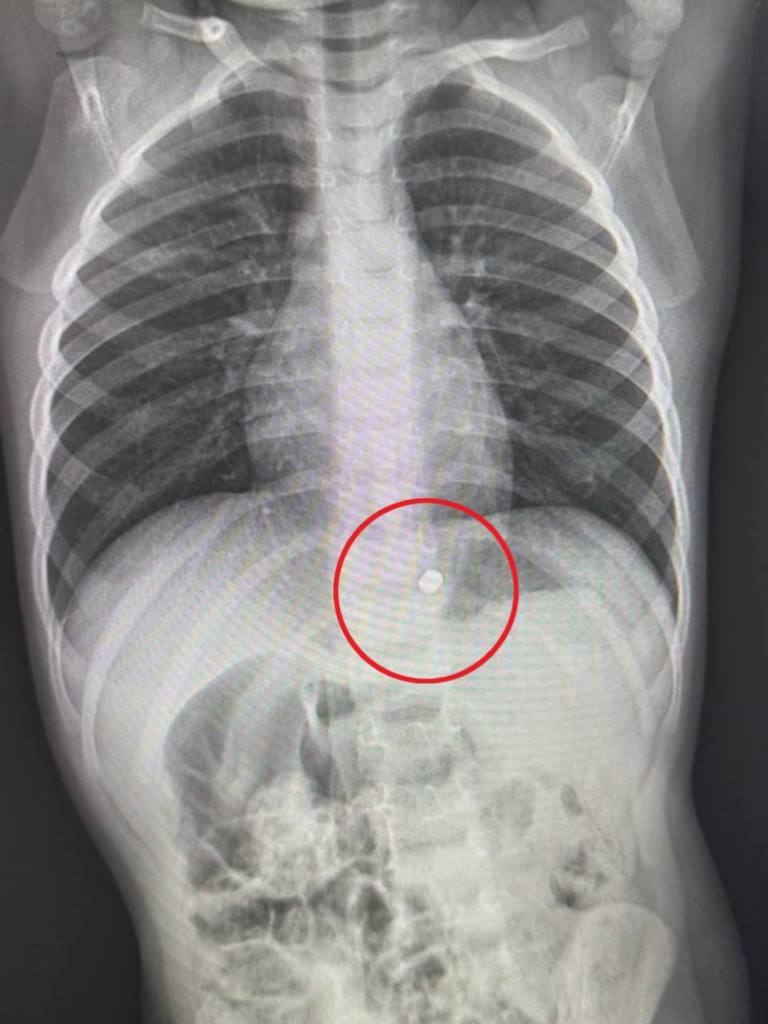

В Детский клинический центр имени Л. М. Рошаля поступил 2-летний мальчик с сильной болью в животе. Как выяснилось, ранее ребенок проглотил два магнита. Рентгеновские снимки подтвердили наличие этих магнитов в области желудка, что потребовало экстренной госпитализации и оперативного вмешательства.

— Мы провели мальчику гастроскопию в условиях операционной. В ходе процедуры мы обнаружили, что магниты сцепились друг с другом через слизистую оболочку, один из них находился в желудке, а другой в пищеводе. Из-за сильного магнитного поля магниты вдавились в слизистую, их было сложно захватить эндоскопическими инструментами. Поэтому мы использовали дистальный силиконовый колпачок, который позволил низвести магнит из пищевода в желудок, где магниты сцепились друг с другом и примагнитились к поднесенному эндоскопу, после были полностью извлечены из организма ребенка. Процедура заняла около 20 минут и прошла успешно, — сказал врач-эндоскопист Анастасия Лазарева.